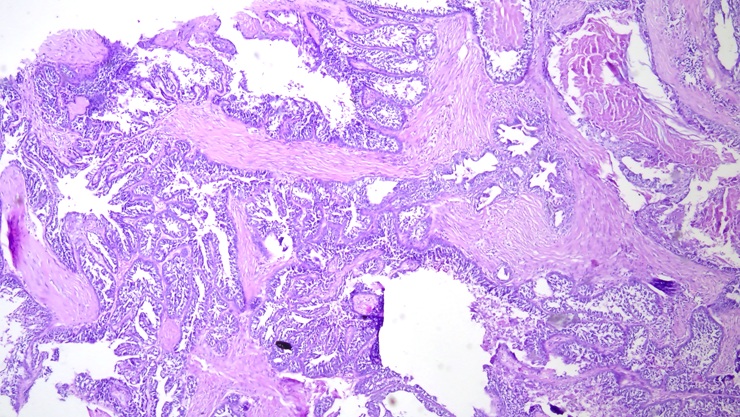

Histopathology

Microscopic study of tissue samples to diagnose diseases and abnormalities.